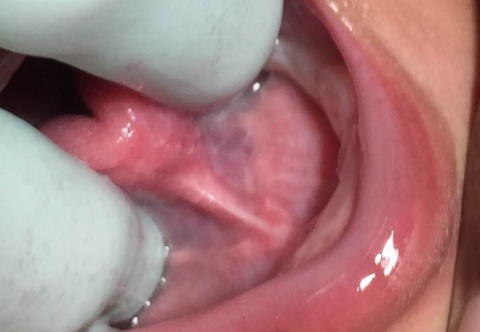

Type 1 Ankyloglossia